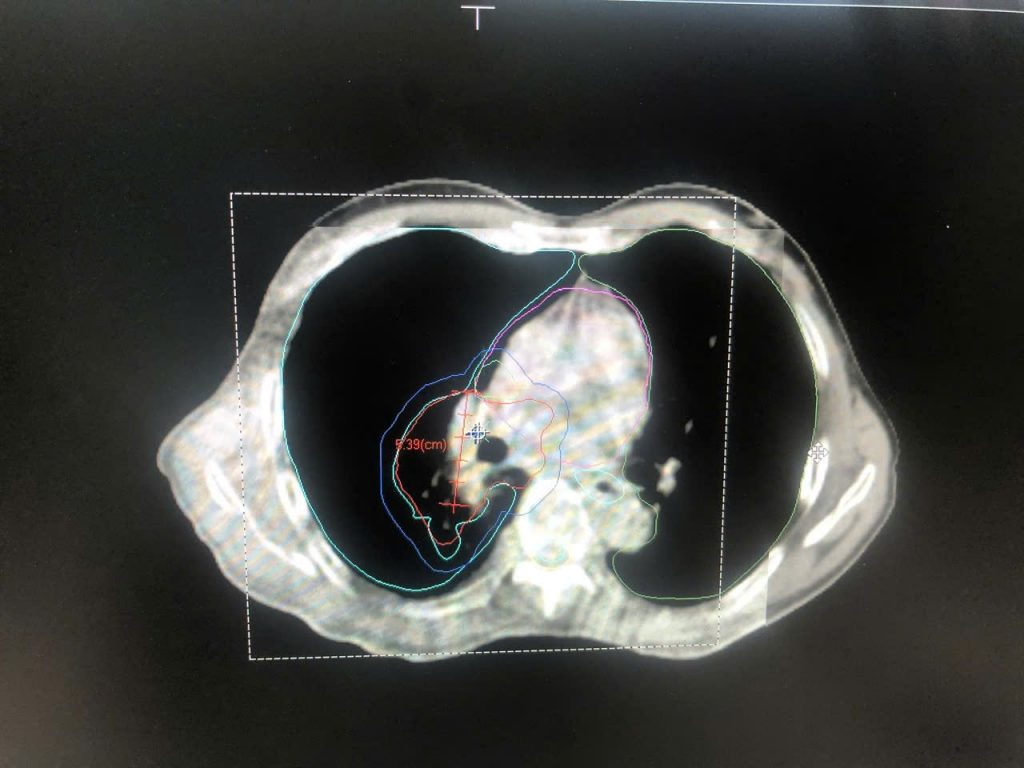

Hình ảnh CT mô phỏng cho bệnh nhân ung thư phổi để lập kế hoạch điều trị

Dựa trên kết quả cận lâm sàng, các bác sĩ khoa Ung Bướu BVĐK Xuyên Á đánh giá đây là ung thư phổi tế bào nhỏ – một loại ung thư diễn tiến nhanh. Khối u ban đầu được đánh giá là u tại chỗ tại vùng, chưa di căn xa.

Qua thăm khám tổng quát cho thấy tổng trạng bệnh nhân H. vẫn tương đối tốt để bước vào liệu trình điều trị. Vì thế, ê – kíp bác sĩ khoa Ung Bướu và khoa Xạ trị Y học hạt nhân đã hội chẩn, quyết định đưa ra phương pháp hóa xạ trị đồng thời với mục đích giúp bệnh nhân đáp ứng tốt, sớm tiêu diệt tế bào ung thư, nhanh cải thiện bệnh. Theo kế hoạch, bệnh nhân H. sẽ được hóa trị 4 – 6 chu kỳ, trong 2 chu kỳ hóa trị đầu tiên thì người bệnh sẽ được xạ trị đồng thời.

Sau một chu kỳ hóa trị và 18 lần xạ trị, khối u của bệnh nhân đã teo nhỏ đáng kể, giảm kích thước đến 60% so với ban đầu. Bên cạnh đó, người bệnh không còn ho ra máu, hết đau ngực, hết ho dai dẳng.